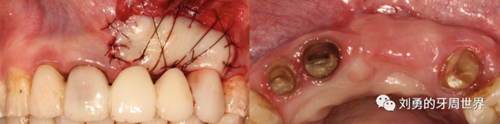

下面是上皮-結(jié)締組織聯(lián)合strip技術(shù)

如下圖:

可見右上前牙植體頰側(cè)無附著齦

為了減少取瓣大小,從上腭取厚一點(diǎn)的齦瓣,然后用刀片平行于表皮表面將齦瓣片切成兩個(gè)厚度一致的齦瓣,然后進(jìn)行移植,這樣切成的兩個(gè)齦瓣一個(gè)有表皮,一個(gè)沒有表皮是單純的結(jié)締組織。如此的片切可以使齦瓣變成雙倍的大小使用,減少了供區(qū)的取瓣面積。